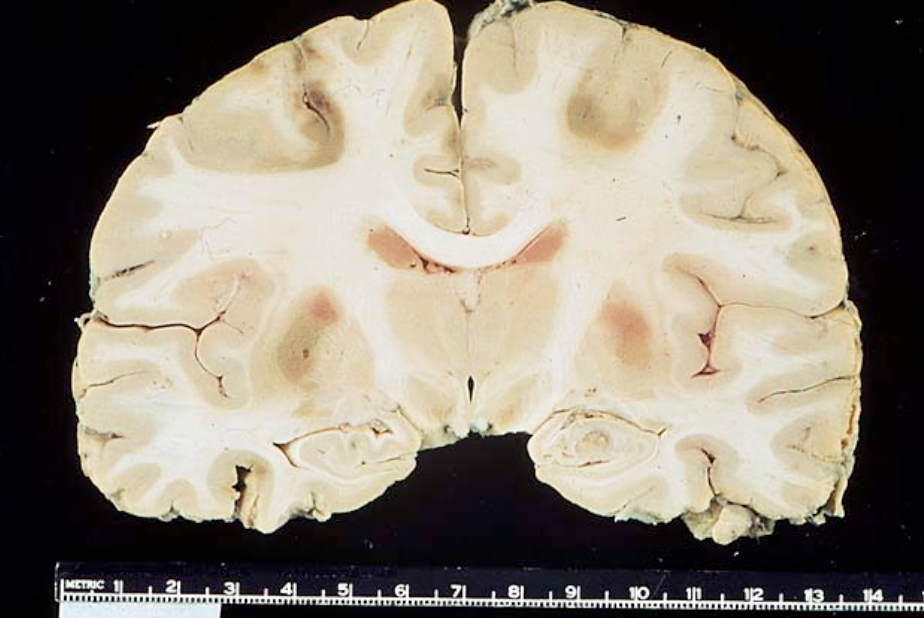

Old guy found down and brought back to life. Died of inability to feed himself. What was the cause?

Watershed infarction. Couldn’t eat due to man in a barrel like weakness and couldn’t get food to his mouth. So sad.

What cells are killed of by transient global hypoperfusion?

Transient shock or cardiopulmonary arrest causes focal ischemic injury to neurons with high metabolic rates:

– Layer 3 and 5 of cortex

– Hippocampus

– Purkinje cells